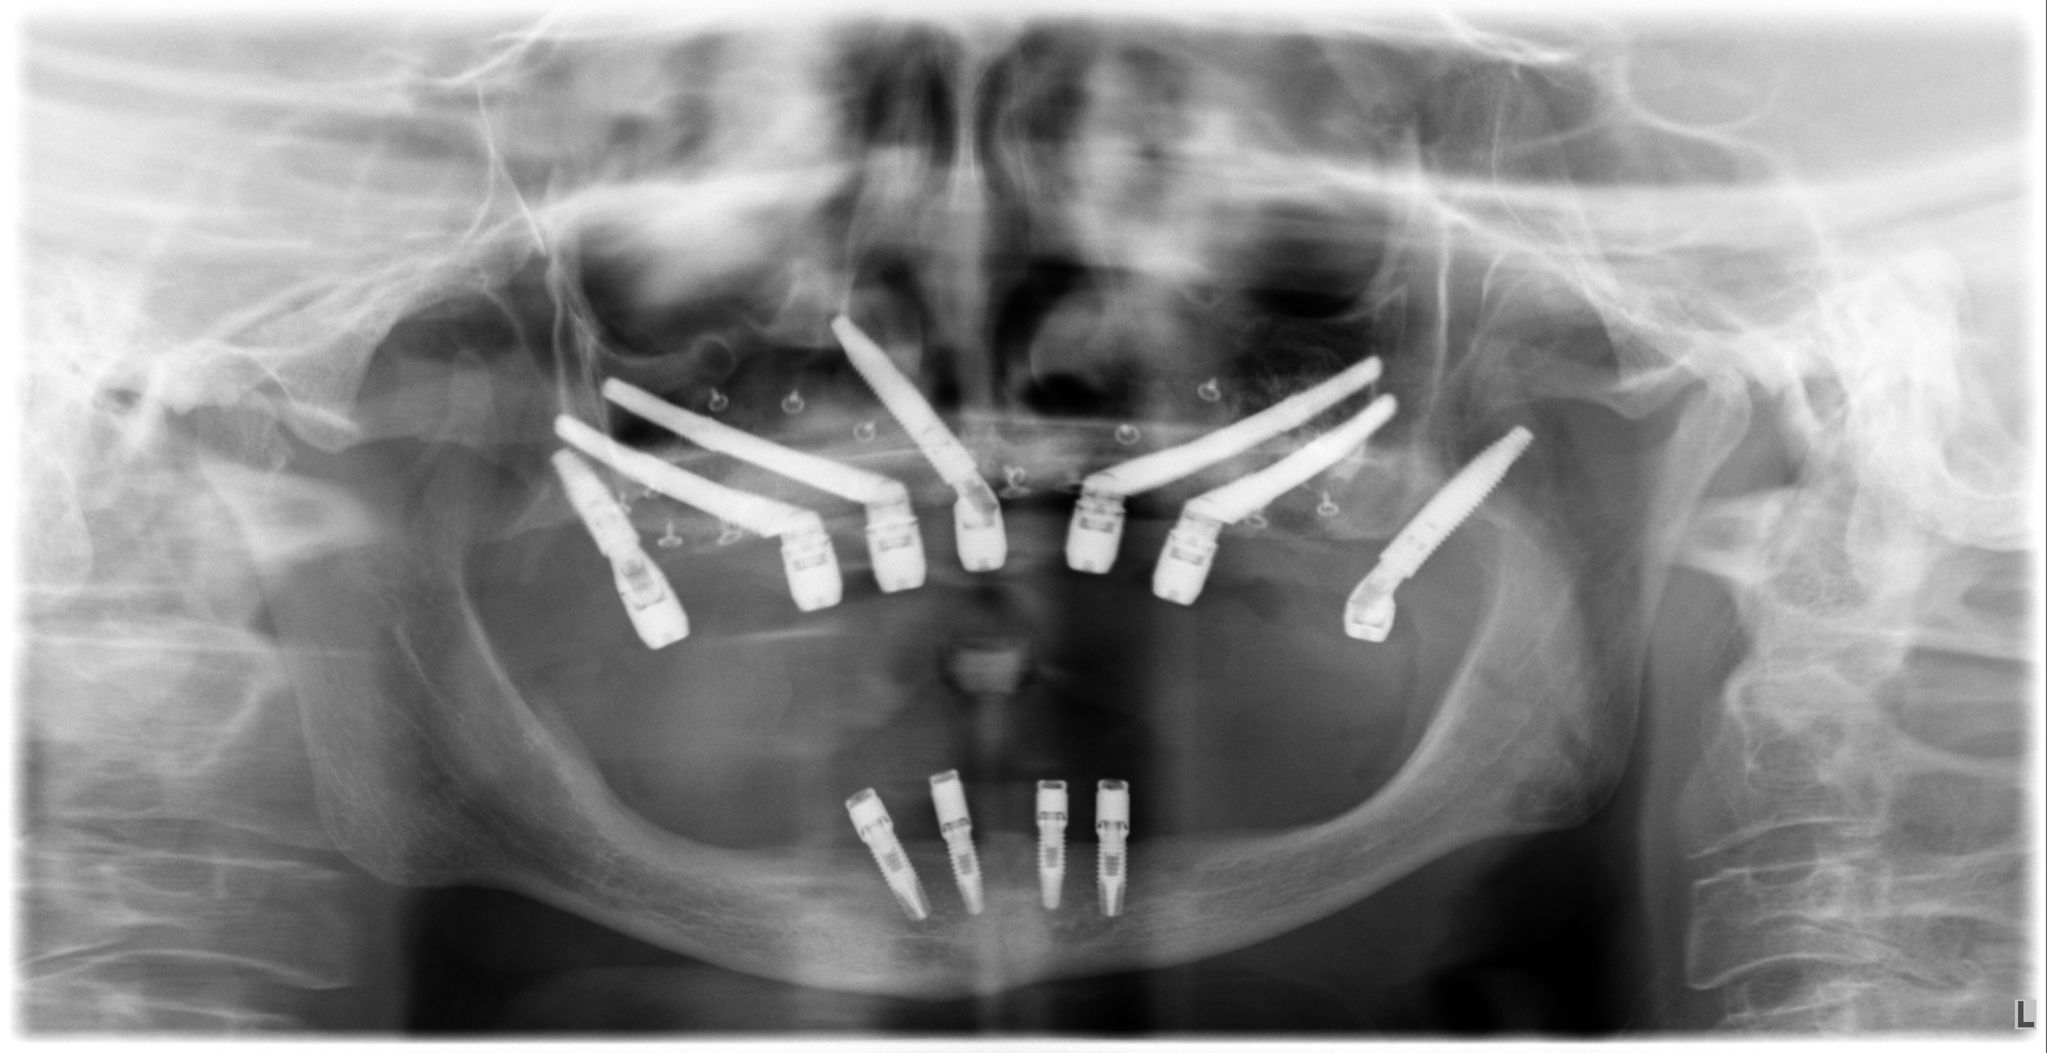

1. Implantes Cigomáticos

Son implantes más largos que se fijan en el cuerpo del hueso cigomático (pómulo). Son la «regla de oro» para tratar maxilares totalmente atróficos. Permiten colocar una arcada completa de dientes fijos sin necesidad de realizar injertos de cadera o calota craneal, reduciendo drásticamente la morbilidad del paciente.

3. Implantes Transnasales

Es una técnica innovadora donde el implante atraviesa una pequeña porción de la cavidad nasal para anclarse en hueso duro opuesto. Se utilizan en casos muy específicos para ganar estabilidad en la zona anterior del maxilar cuando el hueso es inexistente.

- Planificación digital y cirugía guiada para máxima precisión.